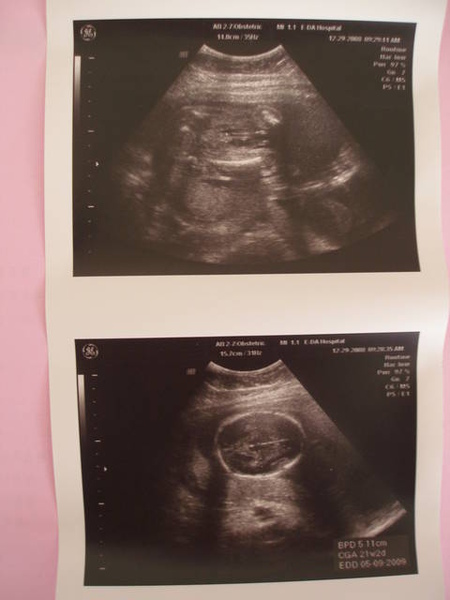

目前是21W2D,胎盤很漂亮,羊水量很充足,

寶寶的嘴唇是OK的,四肢健全,器官發展也很棒~

腦部的狀況也是不錯的。

醫生預計下回再看體重會比較精準,所以這次就還不知道柚子是幾斤兩囉

補充一下:唐氏症篩檢報告是1/6427。正常